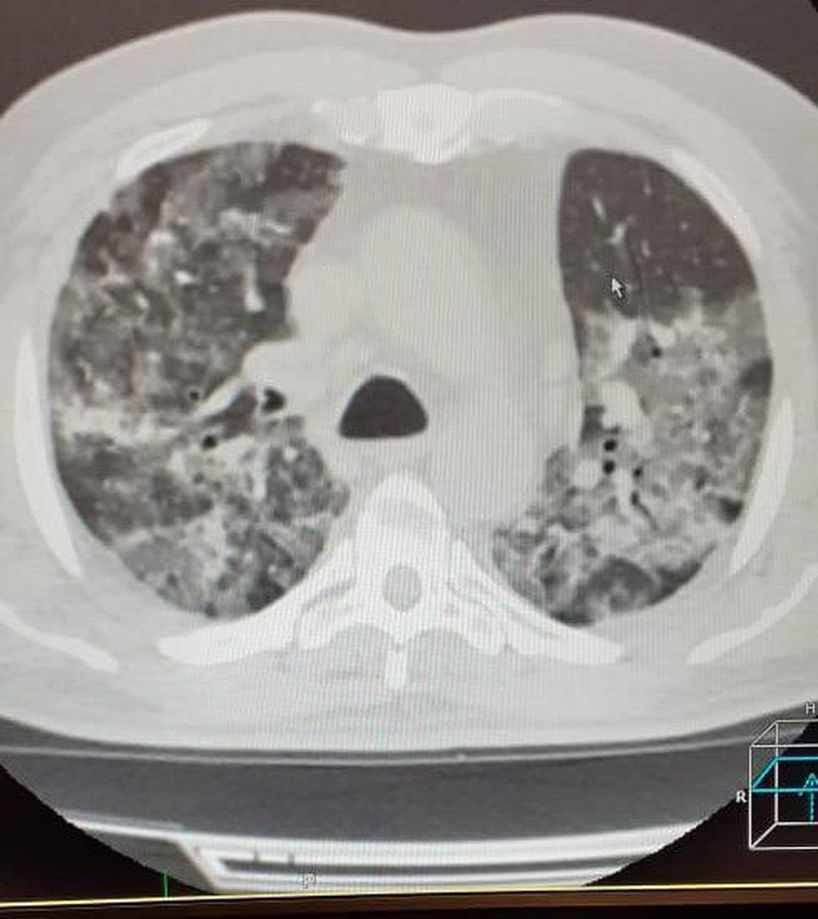

COVID-19

Buzlu cam..

Evet